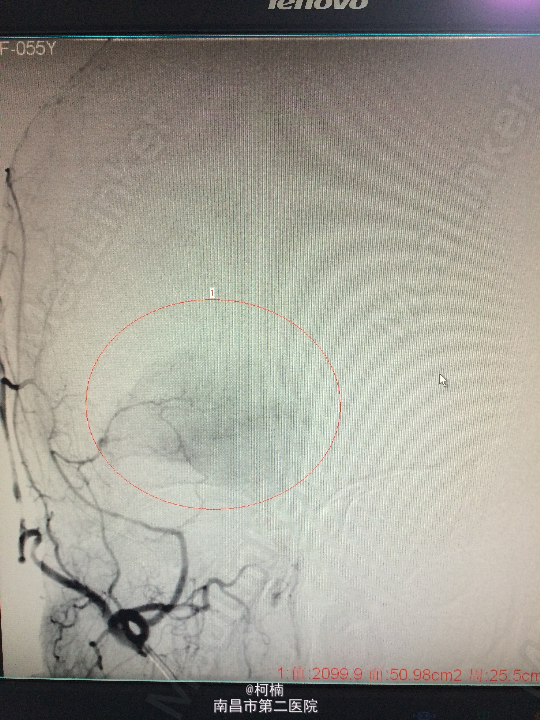

诊断:右侧小脑脑膜瘤 处理:先行介入栓塞肿瘤供血动脉,再行开颅手术治疗,术后予组织病理检查,提示:脑膜瘤